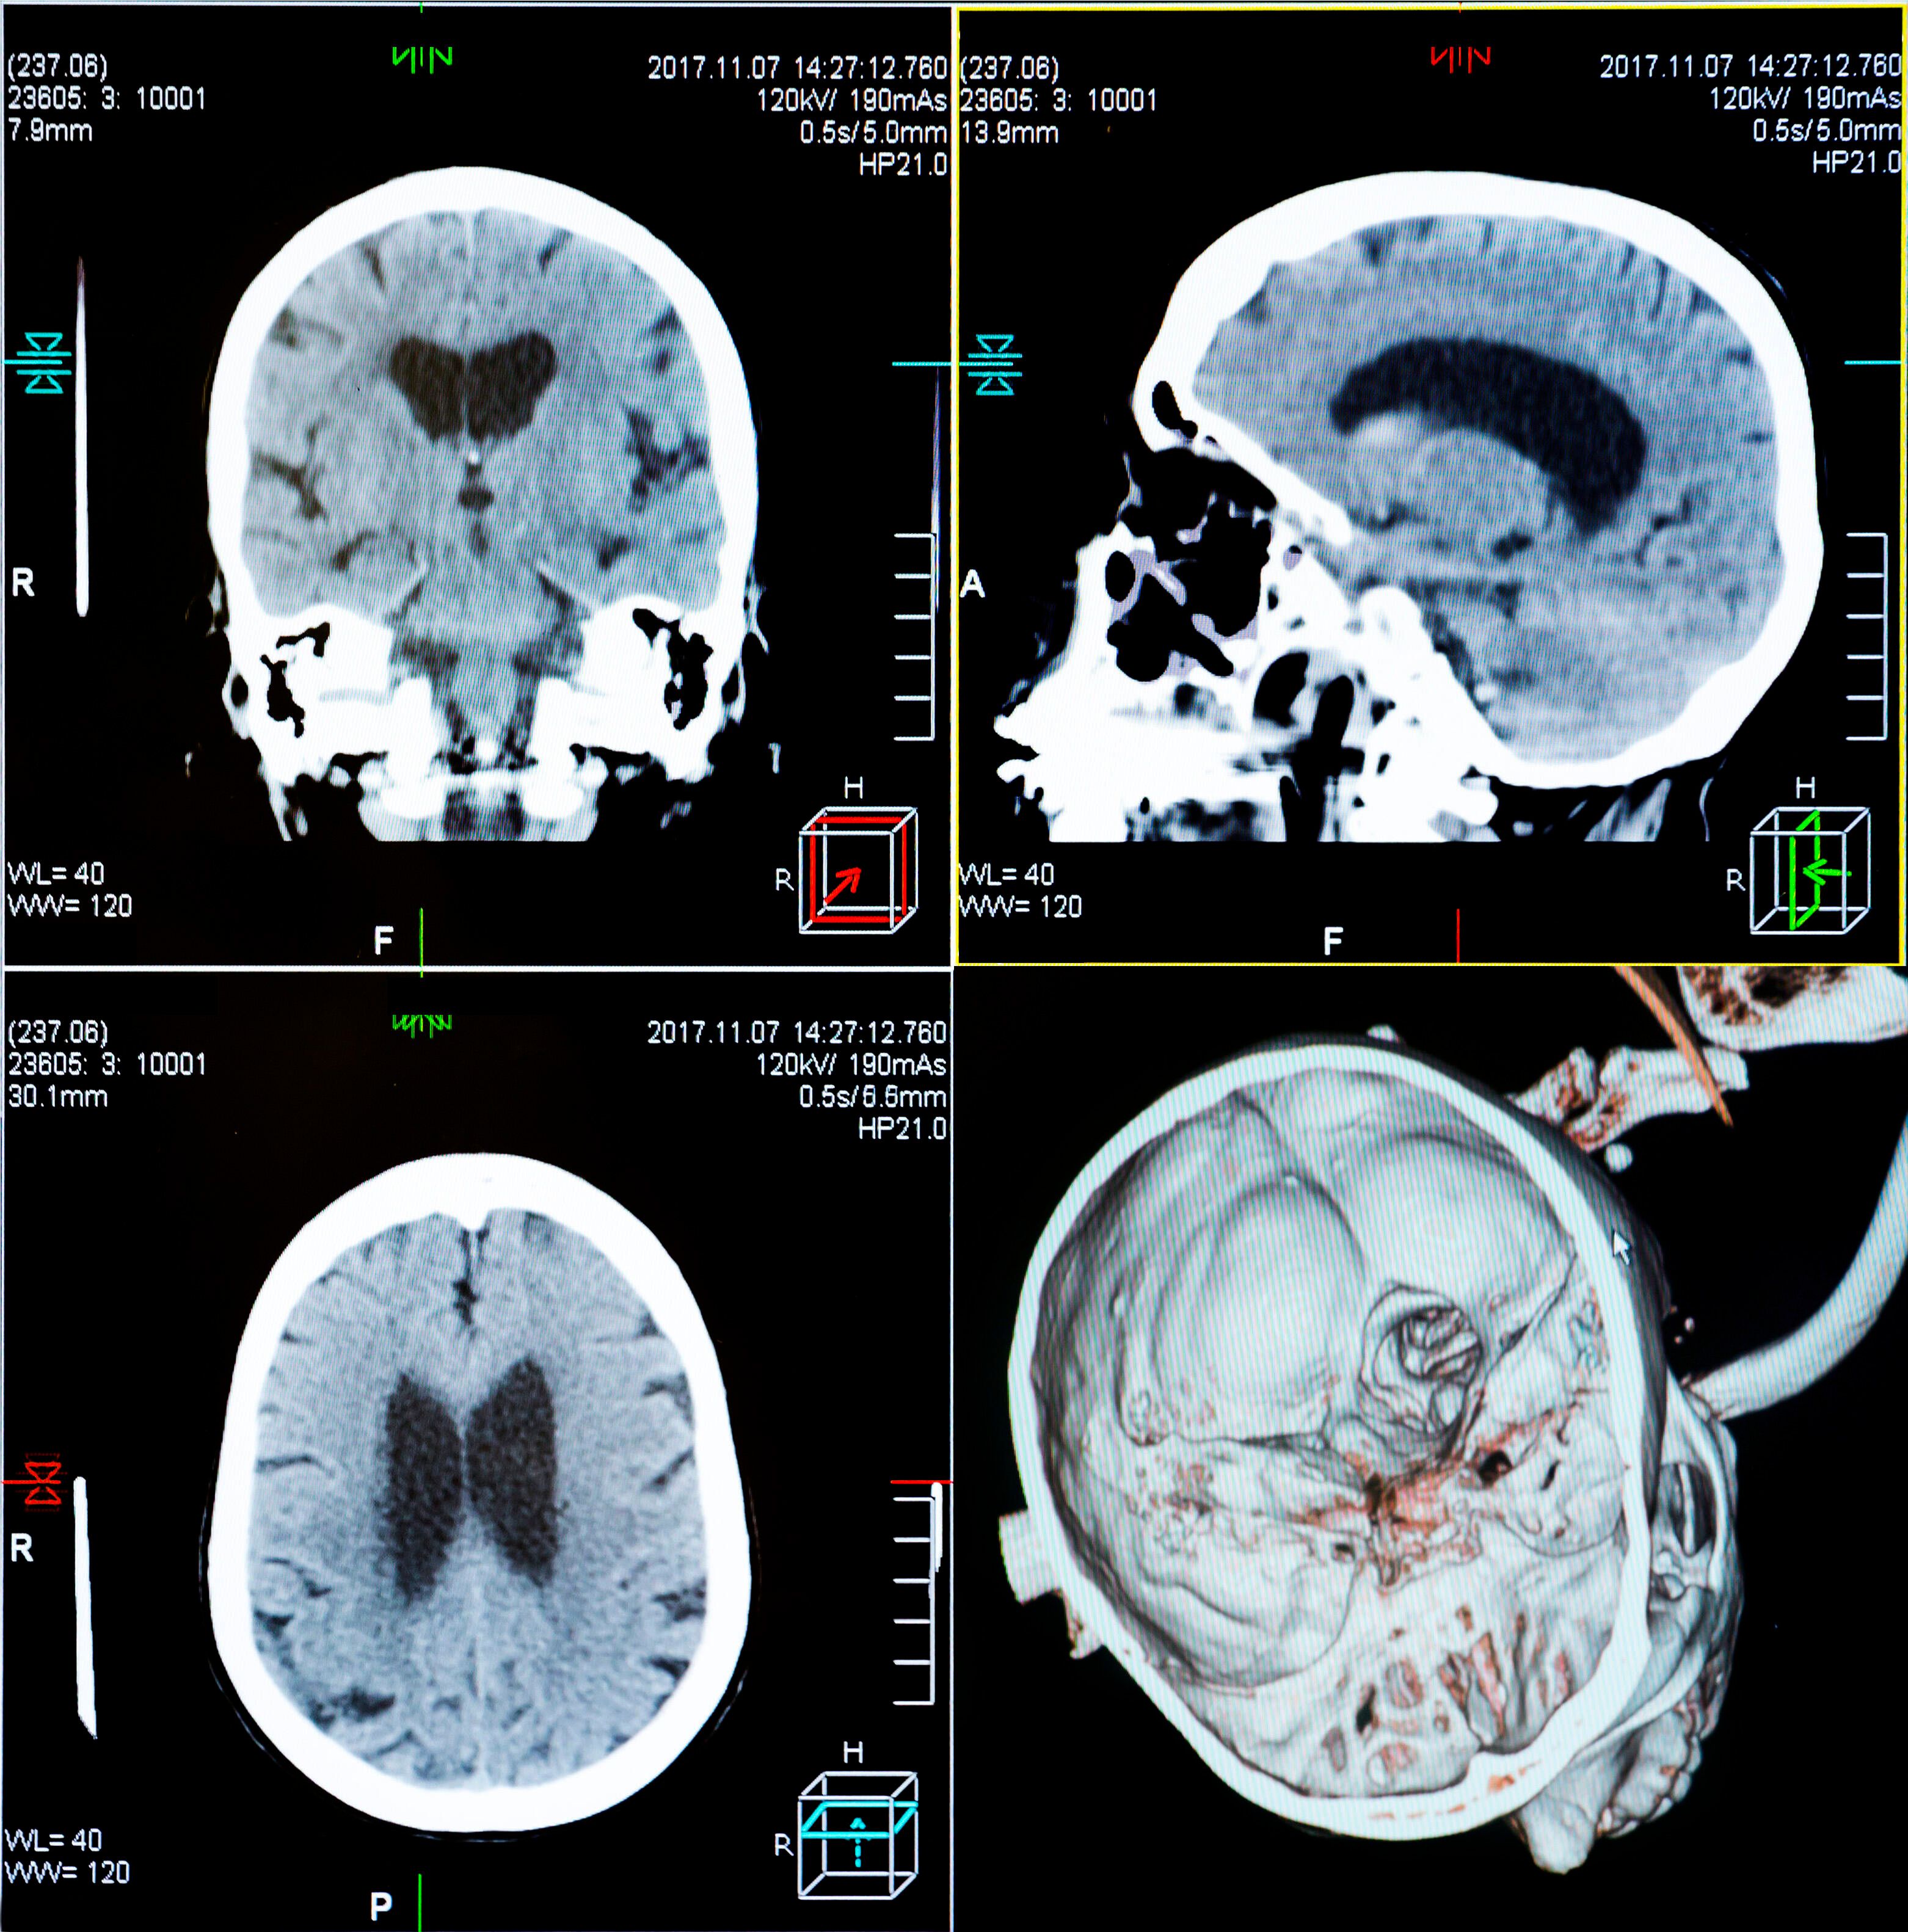

Die tragische Geschichte des jungen Lucas, bei dem im Alter von nur fünf Jahren eine besonders aggressive Form von Hirntumor entdeckt worden war, nahm ein glückliches Ende. Das "diffuse intrinsische Ponsgliom" (DIPG) gilt als unheilbar und hat für 98 Prozent der Patienten tödliche Folgen: Den meisten Betroffenen bleiben nur noch neun bis zwölf Monate zu leben, wie die Universitäre Medizin Zürich auf ihrer Website schreibt. Besonders perfide: Diese Tumorform tritt vor allem bei Kindern auf.

Auch Lucas gaben die Ärzte bei der Diagnose nur wenig Zeit zu leben, wie die "Bild" berichtet. Ein kleiner Funke Hoffnung bestand jedoch noch: Im Rahmen einer klinischen Studie erhielt Lucas nach dem Zufallsprinzip das Medikament Everolimus zugeteilt. Dabei handelt es sich um ein Chemotherapeutikum, das bisher bei DIPG nie angeschlagen hatte.

Tumor ist heute nicht mehr nachweisbar

Und tatsächlich: Lucas reagierte auf das Medikament ausgezeichnet, sein Tumor begann zu schrumpfen. Heute, sieben Jahre später, ist der Krebs nicht mehr im Körper des Kindes nachweisbar – ein medizinisches Wunder und das erste Mal, dass ein Mensch den aggressiven Krebs besiegt hat. Sein Arzt, Jacques Grill, sagt: "Lucas hat alle Hürden überwunden. Sein Fall gibt vielen Menschen eine wahre Hoffnung."

Everolimus blockiert ein Protein, das unter anderem das Wachstum von Krebszellen fördert. Warum das Medikament bei Lucas so effektiv war, ist bisher nicht bekannt. Möglicherweise war es eine Mutation seines Tumors, die seine Zellen empfindlicher für Everolimus machte.